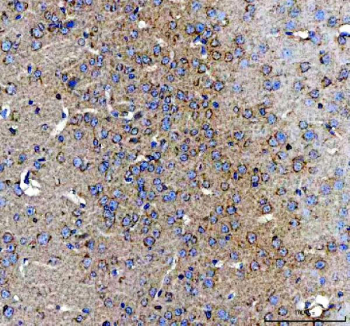

IHC staining of FFPE mouse brain tissue with Amphiregulin antibody. HIER: boil tissue sections in pH8 EDTA for 20 min and allow to cool before testing.

IHC staining of FFPE rat brain tissue with Amphiregulin antibody. HIER: boil tissue sections in pH8 EDTA for 20 min and allow to cool before testing.